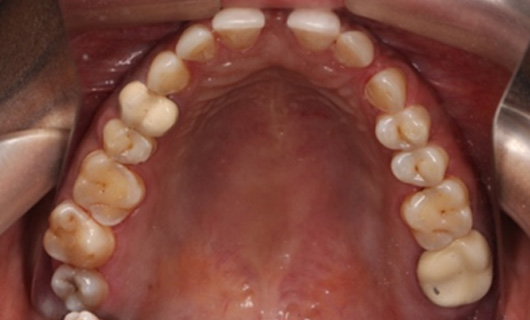

Like braces, Invisalign Braces straighten teeth by placing trays of special material over the teeth in their natural position. A gentle and constant force is used to move the teeth into the desired position without having to go through the hassle of metal wires and brackets. Through digital scanning, they are customized for every patient. Over time, they become a part of the body, since they are so snugly fitting. You are free to eat and drink anything since you will be removing all foods before every meal.